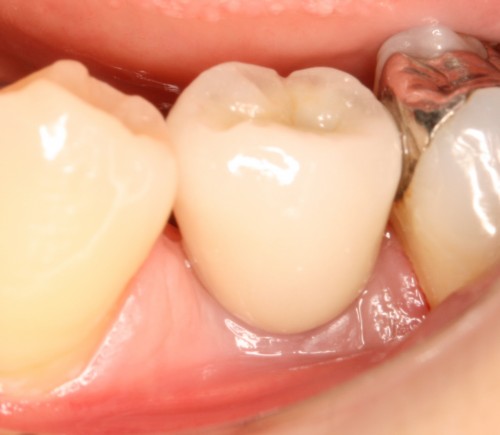

被せ物装着

同全体写真

同パノラマ写真

被せ物装着後歯肉の盛り上がり